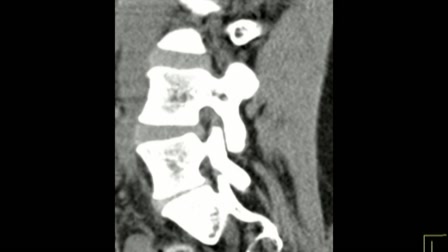

Gerincbarát tornák gerincsérvvel okosan

Gerincbarát tornák gerincsérvvel okosan. www.gerincem.hu